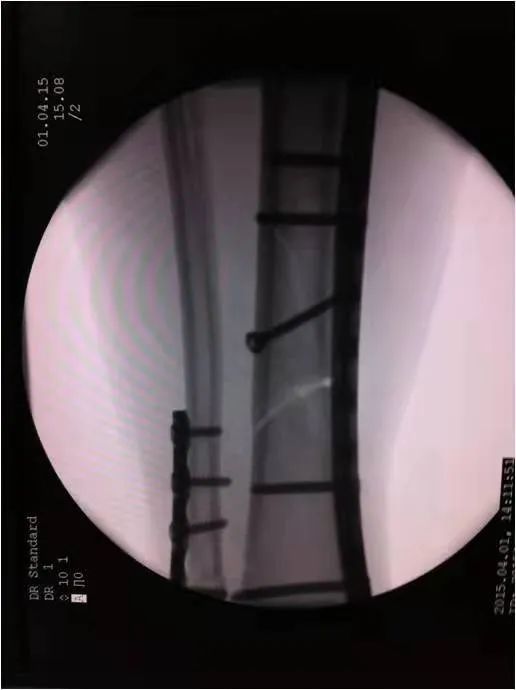

如采用傳統(tǒng)手術(shù)需大范圍剝離軟組織,手術(shù)切口在18公分,損傷面大,影響骨折愈合。經(jīng)過(guò)科內(nèi)術(shù)前討論后與患者及家屬溝通后,呂國(guó)福主任決定行小切口微創(chuàng)鈦板植入內(nèi)固定手術(shù)治療,術(shù)中植入內(nèi)固定物并剝離軟組織,此方法對(duì)周?chē)つw破壞小,手術(shù)切口最小僅0.5公分,極大降低皮膚壞死及后期出現(xiàn)骨不連發(fā)生幾率,從而達(dá)到解剖復(fù)位。

在急診科,檢驗(yàn)科,麻醉科共同努力下,僅用一小時(shí)完成整個(gè)手術(shù),術(shù)中出血量少、過(guò)程順利,手術(shù)非常成功。術(shù)后,呂國(guó)福主任數(shù)次查房,仔細(xì)查看患者的傷口愈合情況,關(guān)心患者的心理狀態(tài),為患者樹(shù)立信心,鼓勵(lì)患者進(jìn)行功能鍛煉。